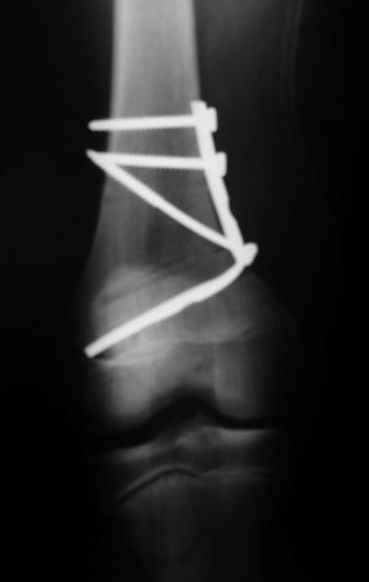

Как вариант решения прогрессирующей вальгусной деформации коленного сустава я бы предложил косую остеотомию дистального отдела бедра с фиксацией пластиной и компрессирующим винтом.

Взгляните на снимки , может быть это вам поможет.

Около 5 лет применяю этот тип дистальной остеотомии бедра для коррекции механической оси Н/К ( более 20 случаев) - достаточно эффективная операция.

Относительно "рубцовой подушки" я имел в виду остатки мениска ( частично вколоченного в дефект мыщелка и фрагменты хряща), все таки на рентгенограммах суставная щель в этом отделе чем то заполнена. Что касается некроза мыщелка бедра, то мне кажется он уже наступил - томограмма ноябрь5.

С учетом всего сказанного - наличия прогессирующего вальгуса конечности, довольно приличного объема движений, имеющегося, вероятно, некроза мыщелка бедра, наиболее рациональным представляется удалить пластину с б\б кости, произвести остеотомию б\б кости с коррекцией вальгуса, разгрузив тем самым наружный отдел сустава, и синтезировать фрагменты голени накостным фиксатором. Максимально тано начать восстановление движений в суставе. Скорее всего рано или поздно речь о протезировании всеже возникнет, но мы хотя бы будем иметь приличную ось конечности.

Сканирование с Тс99 поможет верифицировать наличие некроза мыщелка бедра, если использовались титановые винты, то магнитно-резонансное исследование будет более информативным. При подтверждении некроза, бедренная или всокая тибиальная остеотомии, очевидно, будут малоуспешны, поэтому альтернатив артропластике похоже не останется. Наблюдений реваскуляризации мыщелка бедра после туннелизации у меня нет, надо покопаться в литературе.